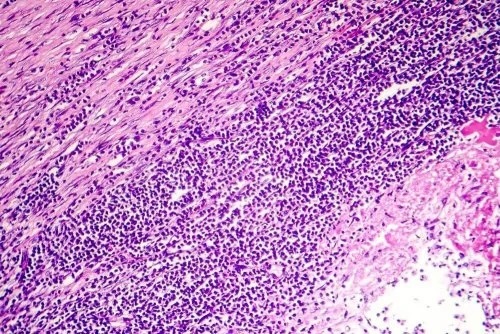

- Pericardita cronică apare ca urmare a îngroșării pericardului sau a unei acumulări de lichide. Durează mai mult de șase săptămâni și poate duce la insuficiența ventriculului drept. Apare un edem în zona abdominală, zona pretibială și glezne. Pericardita cronică apare atunci când în jurul inimii se formează țesut fibros, care o comprimă și crește presiunea în venele care transportă sânge. Astfel, lichidul pericardului stagnează și se acumulează în alte părți ale corpului la ieșire.

În aproximativ 80% din cazuri, este imposibil să se stabilească cauza pericarditei. Însă, este foarte comun ca originea sa să fie rezultatul unui tip de infecție. Este foarte probabil să fie o infecție virală. Poate exista și o infecție bacteriană, dar într-o măsură mai mică. Foarte rar pericardita poate fi urmarea unei infecții fungice.

În alte cazuri, pericardita este rezultatul direct al unui atac de cord, al unei intervenții chirurgicale cardiace sau al unui traumatism în zona toracică. Uneori, pericardita poate proveni din inflamația miocardului, radioterapia toracică sau utilizarea anumitor medicamente.